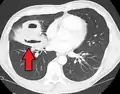

| Computed tomography (CT) scan of chest showing bilateral pneumonia with abscesses, effusions, and caverns. 37-year-old male. | |

Lung abscesses are often on one side and single involving posterior segments of the upper lobes and the apical segments of the lower lobes as these areas are gravity dependent when lying down. Presence of air-fluid levels implies rupture into the bronchial tree or rarely growth of gas forming organism.

Pulmonary abscess on CT scan